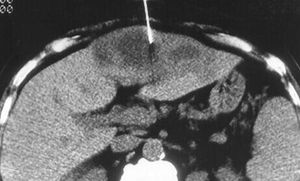

يكون المرضى المصابون بالداء السكري في خطر عالٍ أيضًا لتطور التهاب الوريد البابي وخراجات الكبد. يُشاهَد خراج الكبد بالإشريكية القولونية في الصورة في الأسفل.

يوصى في الخراجات داخل البطن، البطنية والحوضية بإجراء المسح المقطعي المحوسب، يمكن أن تفقد الخراجات في الأمواج فوق الصوتية.

يبدأ الإفراغ الجراحي الملائم من أجل الخراجات الكبدية باستخدام نزع الغطاء بطريق الإحليل transurethral unroofing أو الشق العجاني perineal incision.